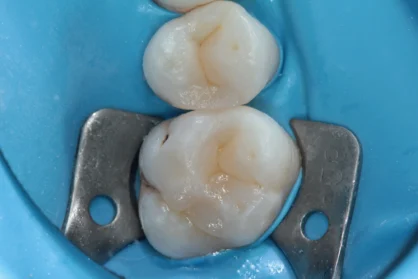

Приклади робіт лікаря-стоматолога

Естетична реставрація. До / після